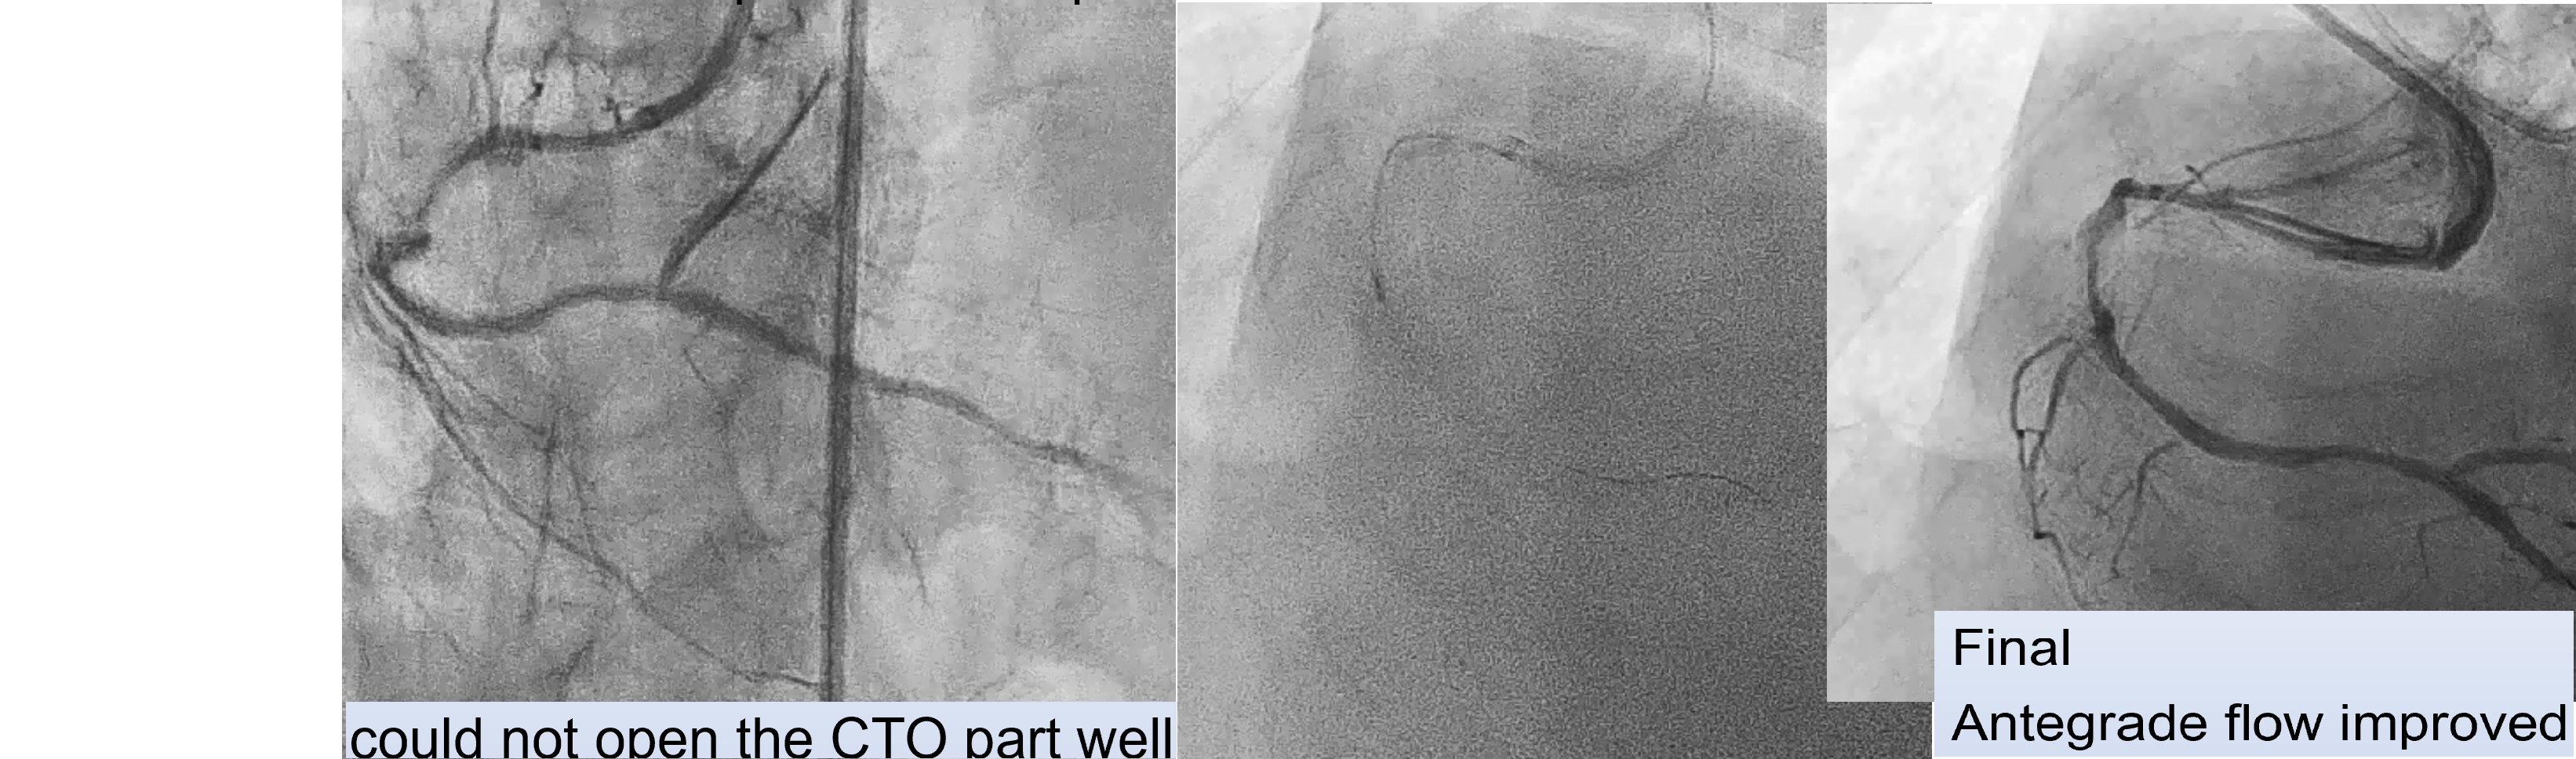

First Procedure: An antegrade approach was initially attempted with wire escalation strategies (using XTA, Fielder FC, Gaia I, II, III, Conquest pro in Cosair), but the wire entered a false lumen. Shift to parallel wire technique with Sasuke. The Gaia III wire eventually reached the distal true lumen. Balloon dilation was attempted, but the CTO segment remained undilatable. IVUS confirmed severe calcification, so a 1.25 mm rotational atherectomy (ROTA) burr was used, which led to mild improvement but still left an undilatable lesion. The procedure was paused because the patient could not tolerate lying flat for an extended time.Second Procedure was performed 3 months later. RCA still showed stenosis despite receiving collateral flow from LAD. Balloon dilation attempts were unsuccessful, necessitating a shift to a 1.75 mm ROTA burr for further plaque modification.After successful lesion modification, further preparation for stenting was performed, followed by the deployment of a 3.0 x 48 mm and a 3.5 x 48 mm drug-eluting stent (DES) in the RCA. Final IVUS confirmed adequate stent placement with good distal runoff. Additional stenting was performed in the LCx and LAD.